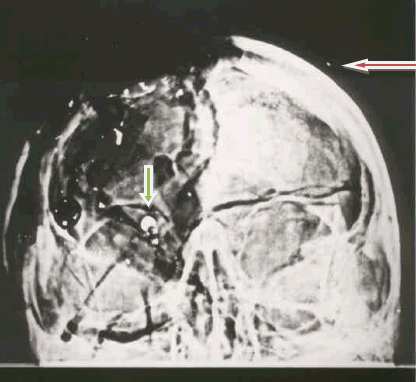

- McAdams claims that no bullet fragments are seen on the left side of JFK’s AP X-ray. (That is JFK’s left—the side of lesser trauma—which would be the reader’s right side.) But this is manifestly false, as I have repeatedly emphasized over many years (see Appendix 5, Figure 1). How do I know that this object is metallic? First, it is also visible on both lateral X-rays; that an artifact would be so spatially consistent—on three X-rays—is quite unlikely. Second, at the National Archives, it does look like metal: its borders are sharp while its optical density and shape are also consistent with metal (compared to the other metallic fragments). Third, the relative densities on the three X-ray views are all consistent with one another. Perhaps McAdams should just take a look (at the Archives). Why is this important? McAdams implies that the absence of such a left-sided fragment suggests that no bullet struck JFK from the front—and that, we all would agree, is indeed a central issue. I would emphasize however that, even though McAdams is clearly wrong about the existence of this fragment, its presence is indeed perplexing and that, by itself, raises some prickly and unorthodox questions.

The most important JFK wounds are those of the head, but McAdams discusses these only tangentially. This is a truly astonishing lack of emphasis. Despite a stunning disagreement with McAdams by most of the professional witnesses, he insists (p. 180) that the back of the head was intact. He also insists that the autopsy photographs and X-rays are authentic, but we now know otherwise (see further discussion below). Images of the back of the head (on the AP skull X-ray) show a bone flap, which probably could swing in and out, remarkably consistent with McClelland’s verbal description of it. I have identified this structure on images (MIDP, p. 227); when this flap was closed, the occipital hole was probably less obvious. I have also identified the skull defect left behind by the Harper fragment—an observation I initially noted with my (then-myopic) naked eyes, but then also confirmed via optical density data. But the real riddles of these wounds (and the X-rays, too) are totally ignored by McAdams. For example, among other inconsistencies, the three pathologists and one radiologist all placed the posterior skull entry wound about 10 centimeters inferior to the trail of metallic debris. (I refer here to the obvious collection of metallic like particles located high in the skull; many of these particles have fuzzy borders, an observation that raises the possibility of a mercury bullet—from the front.) Additional paradoxes are cited in my unanswered letter (see Appendix 8) to Max Holland, another writer who is cited approvingly by McAdams (p. vii).

The skull X-rays themselves are quite consistent with such a right temple entry. The small metallic particles in these X-rays appear to align with just such an entry site. Even more intriguing, this extrapolated line seems to pass through a notch in the skull (the right forehead) that I noticed on the X-rays (for my sketch, see Killing Kennedy by Harrison Livingstone, p. 102). Furthermore, Boswell also sketched missing bone at precisely this site (when he drew on a skull model for the ARRB). There is one last tantalizing clue: the largest metal fragment should have the greatest range—and so it does. The lateral skull X-ray clearly shows that the largest authentic metal fragment (not the small one correlated with the 6.5 mm object within JFK’s right orbit on the AP X-ray) lies near the back of the head—which is consistent with a frontal shot.

As stamp collector I strongly object, on multiple levels, to this characterization. First, I have done precisely what McAdams has advised (p. x), i.e., “focus on the hard data.” I have repeatedly examined the autopsy materials at the National Archives (online: “20 conclusions after 9 visits”), yet McAdams has unfailingly ignored this data. Even more damning though, these data from the Archives are not theoretical (no conspiracy theorist here); rather, they are observational and experimental (perhaps I am a “conspiracy experimentalist”), replete with hundreds of measurements. Furthermore, these data can in principle be reproduced by anyone with access to the autopsy X-rays. (I have seen an optical densitometer at the Archives, which they might loan to McAdams; even a nonscientist can quickly learn to use it—with minimal instruction.) The use of optical density measurements in radiology is an old science (for this history see Appendix 10) and data acquisition itself is rather trivial. After calibrating the device (a simple matter—which I often did during my work), the X-ray is positioned and a reading is taken. For the 6.5 mm object within JFK’s right orbit (on the AP X-ray) I have done this many, many times, typically in the presence of multiple witnesses: an ophthalmologist, an astronomer (who employs optical density measurements in his specialty), and multiple staff members from the Archives. These simple data are astounding: the apparent metallic length of this 6.5 mm object (from front to back), implied by even a single measurement, is radically inconsistent with reality (it is far too long). At this juncture, Sherlock Holmes, from my favorite childhood tale (The Sign of the Four)is precisely on target: “Eliminate all other factors, and the one which remains must be the truth.” In this case the conclusion is unambiguous: this 6.5 mm object must have been superimposed in the darkroom and must therefore be a forgery (Assassination Science, edited by James Fetzer, pp. 120-137). Even Larry Sturdivan, the ballistics expert who testified before the WC (and who is even cited by McAdams, p. 130) could not explain this object.

I’m not sure just what that 6.5 mm fragment is. One thing I’m sure it is NOT is a cross-section from the interior of a bullet. I have seen literally thousands of bullets, deformed and undeformed, after penetrating tissue and tissue simulants. Some were bent, some torn in two or more pieces, but to have a cross-section sheared out is physically impossible. That fragment has a lot of mystery associated with it. Some have said it was a piece of the jacket, sheared off by the bone and left on the outside of the skull. I’ve never seen a perfectly round piece of bullet jacket in any wound. Furthermore, the fragment seems to have greater optical density thin-face on [the frontal X-ray] than it does edgewise [the lateral X-ray]…. The only thing I can think is that it is an artifact (MIDP, p. 266).

Of course, Sturdivan’s conclusion is just more vital evidence that McAdams has decided to cull; even worse, though, he does not so inform his readers. To date, no one (unless forgery is invoked) has been able to explain this bizarre 6.5 mm object on JFK’s AP X-ray. Even the experts for the ARRB (including the forensic radiologist, John J. Fitzpatrick, who was visibly troubled by this strange feature) could not explain this fantastic object). So we are left with this conclusion about this hardest of “hard” evidence: an odd event occurred in JFK’s X-rays that has never, before or since, been seen in the history of radiology. Furthermore, even the best experts in forensic radiology still cannot explain it. And this is what McAdams—who has never claimed to be an expert on X-rays—takes for “hard” evidence of no conspiracy. (Since Speer’s essays overlap with these issues, readers might also review my response to Pat’s protests at here.) Also recall that Helpern, in over 60,000 cases, had never seen an exit bullet produce a wound like that in JFK’s throat. That might raise an acutely troubling question about the lone gunman scenario: How likely is it that two such unprecedented events would spontaneously appear in just one case?

McAdams asks whether the photos and X-rays had changed in the interval between the autopsy and the Clark Panel (1968). He has an excellent reason for asking this question: the perplexing 6.5 mm object within JFK’s right orbit had not been reported at the autopsy, even though the chief goal of the X-rays had been to identify precisely such objects. Moreover, McAdams never asks the most embarrassing question: Of the many individuals who saw the X-rays that night, why did no one discuss, report, or recall this bizarre object?

To make matters even worse for this “hard” evidence, I made one more critical observation on a lateral JFK skull X-ray at the Archives, an observation that any amateur could easily reproduce (including several anti-conspiracists who have since visited, yet apparently failed to look): this left lateral is obviously a copy, not an original. Why does that matter? First, the Archives claim that it is an original, so something is clearly amiss. Secondly, though, if it is a copy, the door would be left wide open to manipulation in the dark room. And how do I know it is a copy? Because a T-shaped inscription was made on the original film by someone (for an unknown reason, but it doesn’t matter); this could only have been done by scraping the emulsion off the film, a fact that would be trivial to see on an original. But here is the problem: the film at the Archives has no missing emulsion! In fact all surfaces (near this inscription) show entirely intact emulsion—which, of course, perfectly describes a duplicate X-ray film. Of course, McAdams has also culled this observation from his data set. He could easily have tested this observation himself—even now, why doesn’t he just book a trip to the Archives?